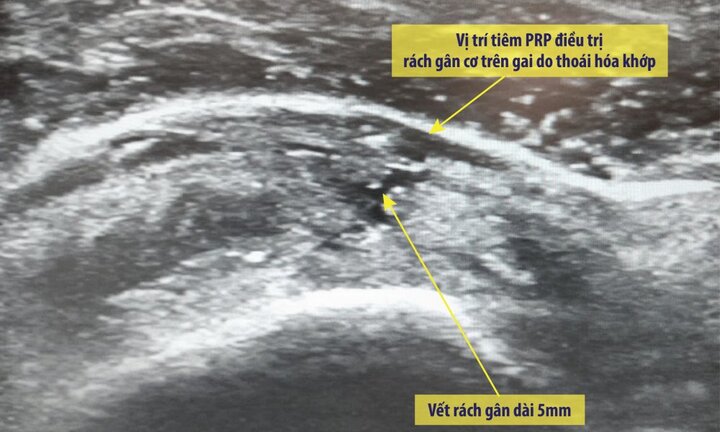

Tiêm huyết tương giàu tiểu cầu (PRP) là biện pháp điều trị an toàn với bệnh nhân viêm khớp, giúp chấm dứt cơn đau nhanh và bền vững.